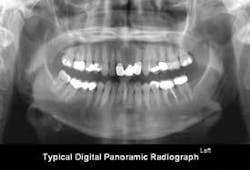

Panoramic radiographs (Fig. 2): The current digital panoramic radiograph devices are excellent, and the radiographs provided by them show an overall, easily understood view of the oral structures. Panoramic radiographs are excellent for initial screening and can provide adequate singular radiographs for some types of patients, especially those with only a few teeth remaining or edentulous patients.